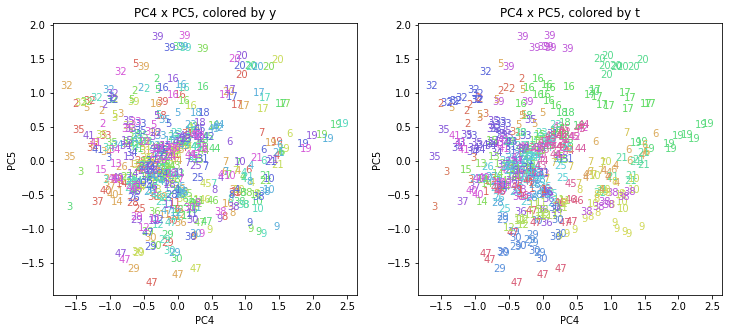

PCAの結果の第n主成分をPCnと表記します。

医療費データの場合と同様に、PCAの結果を見やすく表示するため、seabornのカラーパレットを使って、年月別、都道府県別に色分けして図示してみます(左側が年月別に色分け、右側が都道府県別に色分け)。PC1~PC8まで表示しました。

都道府県番号の表示

上の色分けだけでは都道府県が区別しにくいので、医療費データの場合と同様に、点の代わりに都道府県番号をプロットした図も描いておきます(色分けは上と同じ)。

医療費データの場合ほどはっきりとはしていませんが、PC2が概ね時間の経過を表す成分で、残りの成分が時点によって変わらない地域の特徴を表す成分となっているようです。

また、PC1×PC3を見ると、47沖縄が他の都道府県からかなり離れたところに位置しており、沖縄の地域差が際立っているのが分かります。これは、以前別の記事で年齢階級のない健診データでPCAを実行した場合と似た結果となっています。